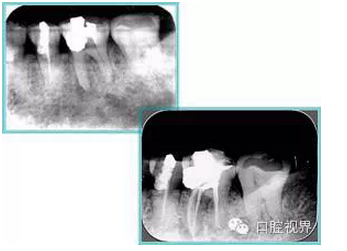

左圖和上圖為干髓治療后牙齒,齲齒疏通后進(jìn)行根管充填。